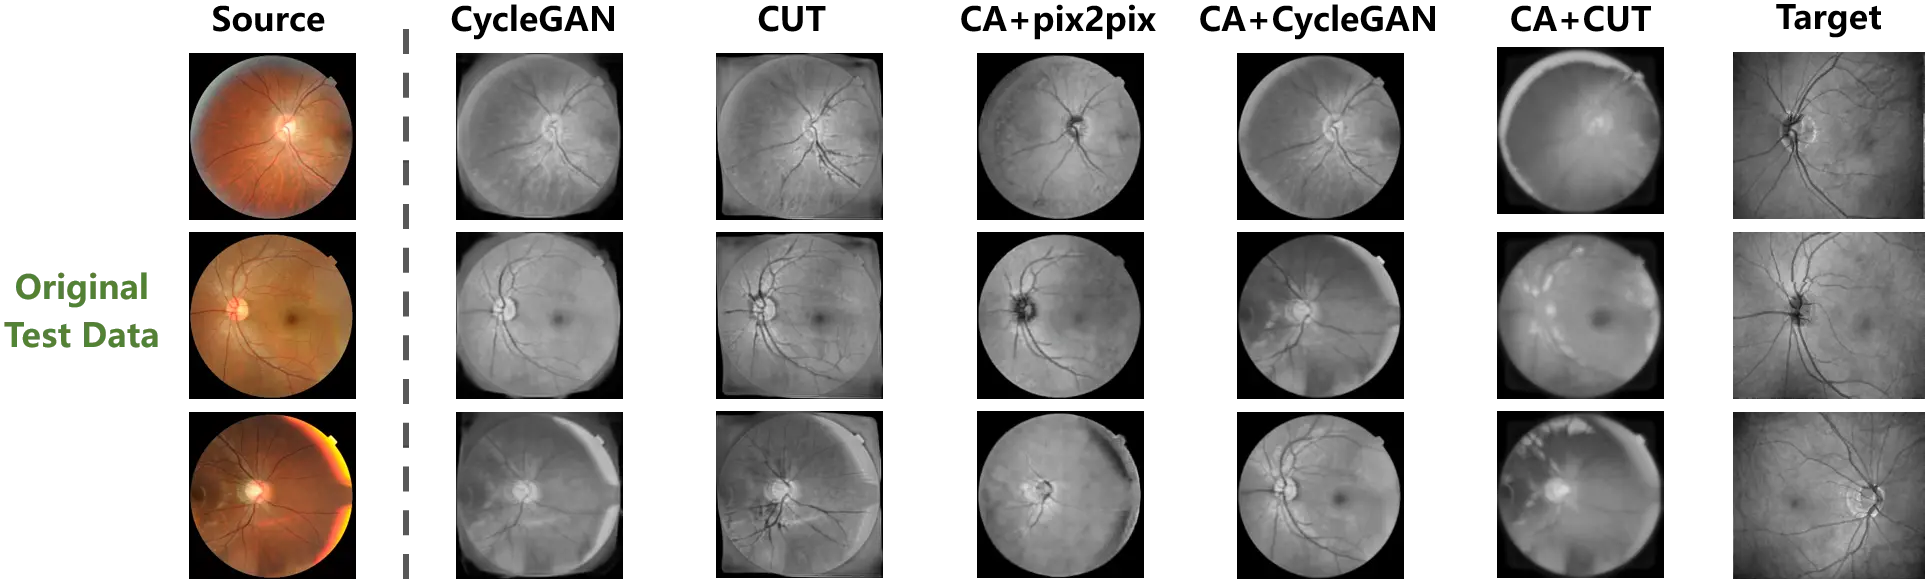

3.2.1 Evaluation with original data

The synthesized outputs of the original test data are exhibited in Figure 5, and the source and target samples are respectively presented in the first and last columns. Although the mappings from the source to the target domain could be learned by the unpaired translation models from the original data, these mappings improperly match the domains. Specifically, the foreground is distributed throughout the entire images of the target samples, while the foreground of the source samples is a circular area in the center. This distribution bias in the training data is regarded as an intrinsic domain shift from the source to the target domain by the translation models. Consequently, as shown in the second and third columns of Figure 5, the learned mappings tried to match the target samples by filling the background of the source samples at the corners. The synthesized outputs of CycleGAN and CUT, which were trained on the original data, thus suffer severely from hallucination in the corner background.

Figure 5. The cross-modality translation tested on the original weakly paired retinal data. The distribution bias misleads the learning of translation mapping to fill up the background of the source samples. And Content adaptation enhances the translation models by correcting the bias.

On the other hand, the proposed method is designed to correct the distribution bias between the source and target samples. In accordance with the fourth to the sixth columns of Figure 5, once the sample distribution is aligned by content adaptation, the mappings between domains are more effectively established by the translation models. The hallucination in the outputs has been significantly constrained by the models trained on the content adapted data. Additionally, using content adaptation, the pix-level correspondence is constructed on the weakly paired data. The paired image translation model of pix2pix is enabled. Furthermore, content adaptation endowed versatility to the translation models, such that superior performances are presented on the original test data.

As pix2pix is not able to be trained on the original data, the corresponding values are absent in Table 1. Content adaptation provided aligned training samples to the translation models, such that pix2pix was enabled and the performances of the unpaired translation models were remarkably improved. The comparison between the results of the original and content adapted data indicates that through correcting the distribution bias in the training data, superior translation mappings were discovered by identical models.

3.2.2 Evaluation with content adapted data

To further investigate the influence of training samples, the test data that underwent content adaptation was also used for the evaluation. Figure 6 exhibits the synthesized outputs based on the content adapted test data. In the first and last columns, the source and target samples are respectively presented.

Figure 6. The cross-modality translation tested on the content adapted retinal data. The paired test data are provided by content adaptation. A comparison between the translation outputs and the target samples is thus presented.

Consistent with the observation in Figure 5, the translation mapping learned from the original data still tried to fill the background of the source samples, while the foreground and background in the source samples were satisfactorily preserved by the models trained on the content adapted data.